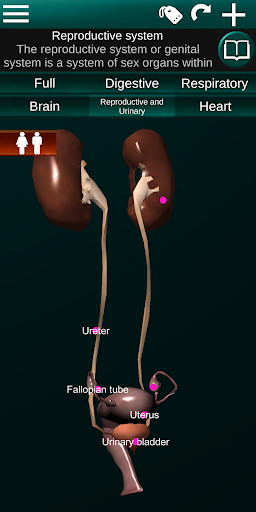

Показує 3D анатомічну модель основні органи людського тіла та опис кожного з них.

* Репродуктивна система, яка включає чоловічі та жіночі репродуктивні органи.

* Порівняйте чоловічі та жіночі органи.